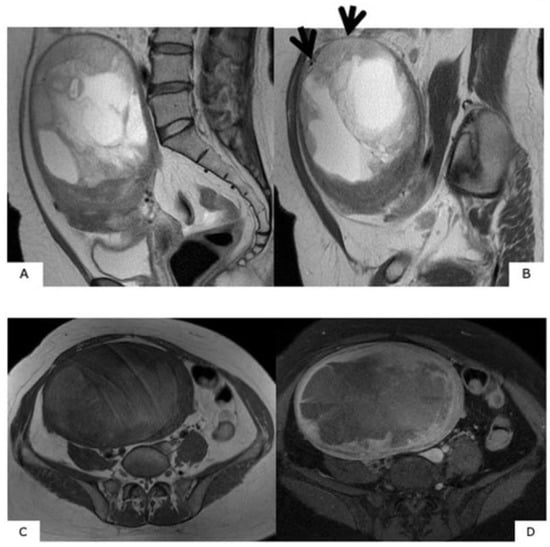

Figure 7.

Magnetic resonance images of low-grade endometrial stromal sarcoma. (A): T2-weighted sagittal section, (B): T1-weighted sagittal section, (C): T2-weighted axial section, (D): diffusion-weighted image. Within the uterine posterior wall myometrium, in T2-weighted images, there are relatively high signals, and in T1-weighted images, a mass with ill-defined borders presenting low signals is observed. In (A) and (C), a low-signal band exists in the high-signal mass, presenting a “worm-like” finding that suggests that the low-grade endometrial stromal sarcoma is penetrating the normal myometrium while interposing itself intratumorally. Reduced diffusion is shown in (D).